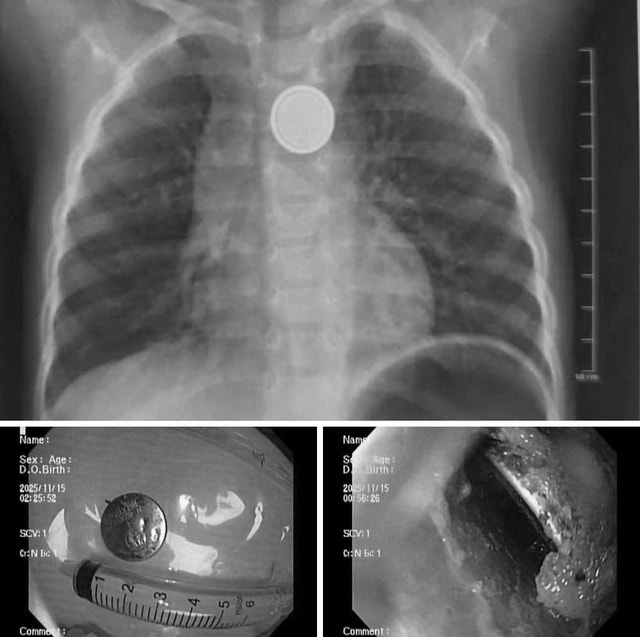

Tại đây, các bác sĩ đã tiến hành chụp X-quang, kết quả cho thấy dị vật kẹt tại thực quản.

Ê-kíp nội soi cấp cứu đã nhanh chóng tiến hành gắp thành công viên pin ra ngoài. Dù được cấp cứu sớm song qua quan sát trực tiếp, e-kip nội soi ghi nhận có vùng ăn mòn, gây loét thực quản.